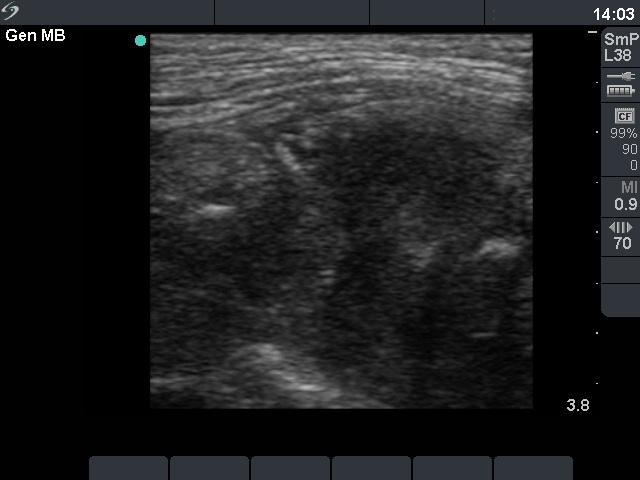

Secondary thyroid carcinomas - Case 15.

Metastasis of a laryngeal adenoid cystic cancer (ultrasonographic picture 5)

Left lobe, longitudinal scan. The previous picture without arrows.